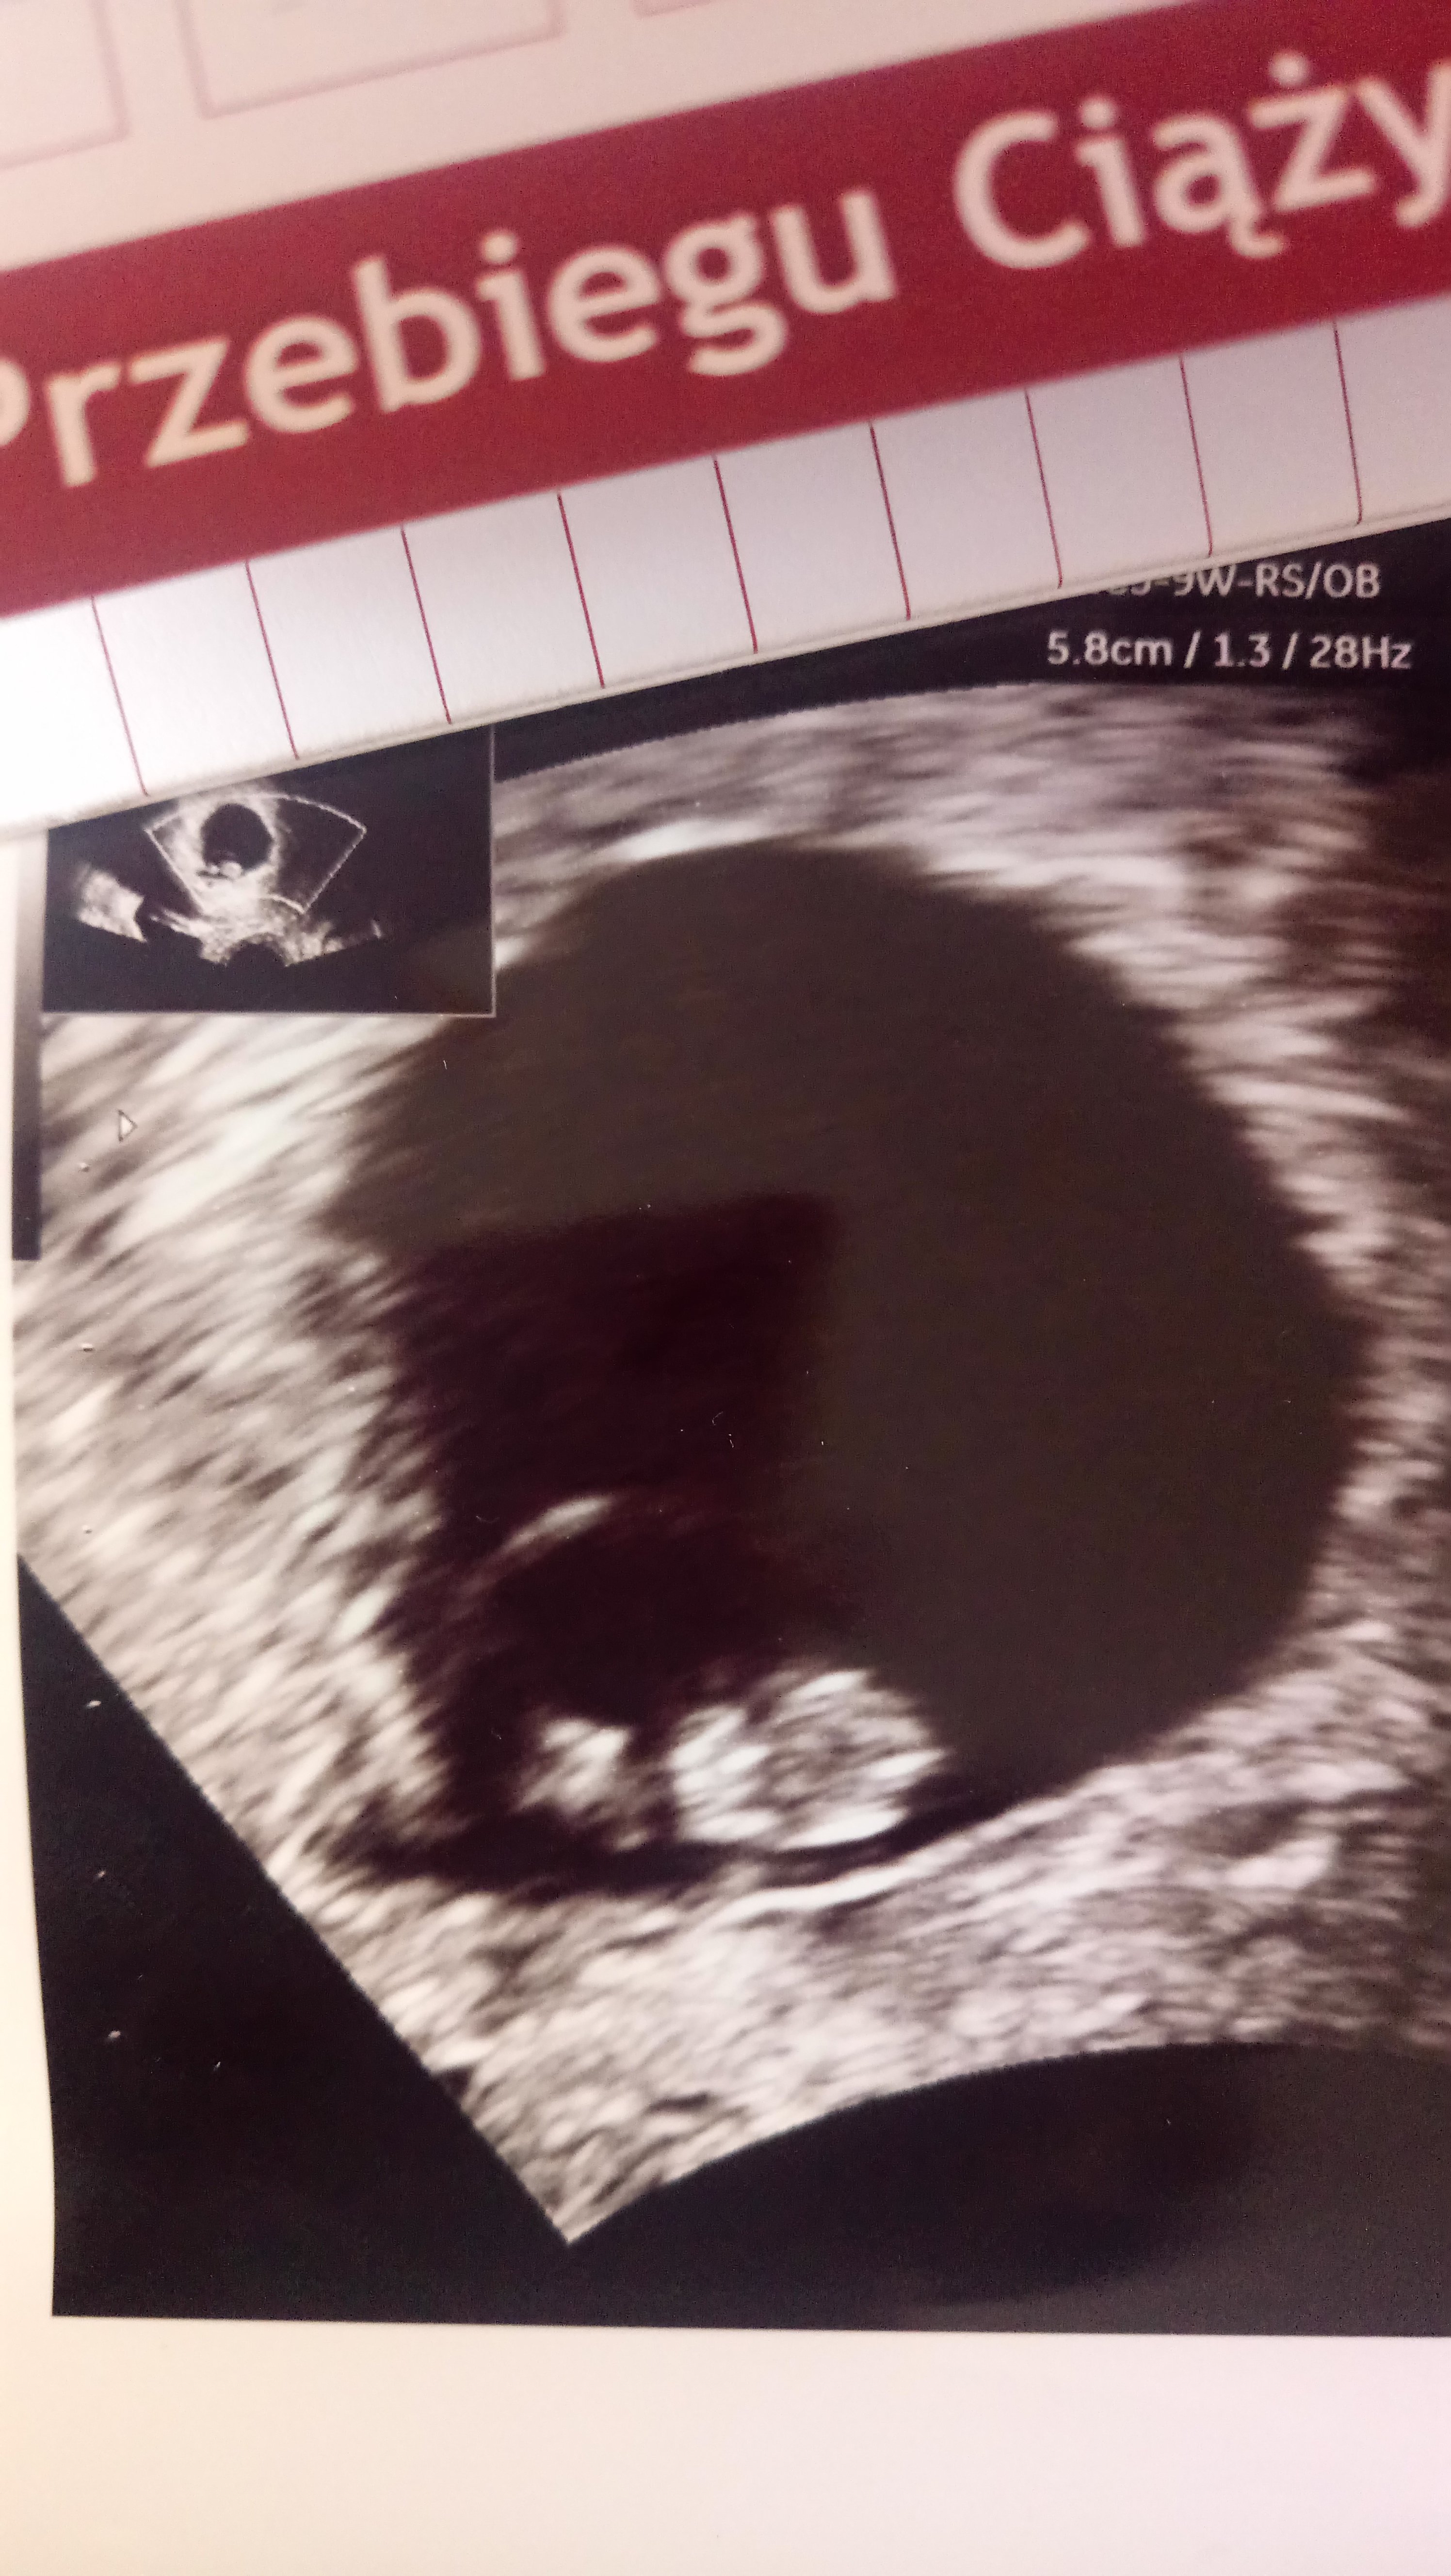

Ale macie fajnie, ja już po u mnie tylko pęcherzyk :( i znowu takie czekanie i stres :( mam powtórzyć betę jutro i jak będzie 8 tys. To wizyta dopiero 12.07 a jak nie będzie to jutro mam dzwonić :/ eeeh znowu się martwię

Ale jedno pozytywne to jest to, ze jest ładny pęcherzyk i w dobrym miejscu

Załączniki

• 8CCE7583-FFB5-4E6D-A0D5-A4E611C3C36B.jpeg

8CCE7583-FFB5-4E6D-A0D5-A4E611C3C36B.jpeg

1 MB · Wyświetleń: 90